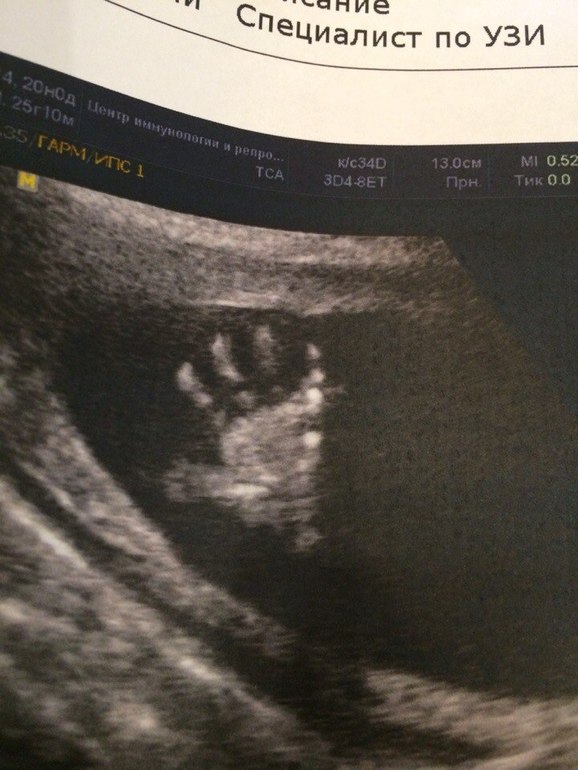

а вот всем приветик от нашего малыша

спасибо,на диске еще есть ступня,жаль не напечатали) и так забавно ,маме щас показывали запись , вот на ладошке даже линии видно,для мамы это вообще чудо техники ,раньше же не было) и вот старший у меня ну очень похож на снимки 3д с УЗИ))